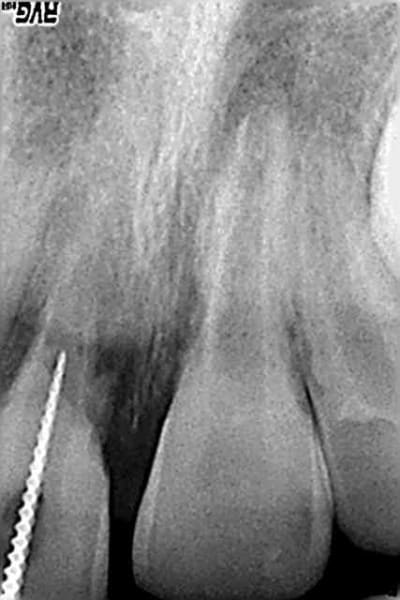

on a entre 7 et 10 ans de croissance osseuse encore, je ne peux même pas te suggérer , en cas d'extraction, une technique de préservation de volume osseux sur un cas comme celui là.

toute considération odf mise à part, je garde la contention sur cette dent, je la fais durer le plus longtenps possible, quand elle est vraiment foutue je la laisserais collée à l'arc odf jusqu'à la fin de la croissance.

ensuite, greffe et implant.

mais il y a le temps.

il y a ici une utilisation du laser possible. j'ai vu un cas traité par un copain de cette manière :

au lieu d'aller farfouiller dans la pulpe, ouverture de la chambre, tirs laser sur la pulpe exposée, MTA par dessus. à 6 mois, apparition d'un pont dentinaire sous le MTA, et apexification simultanée. reste à voir dans le temps ce que ça donnera.

intéressant

mais ds ce cas de pulpe nécrosée et purulente ,faut bien nettoyer,non?

ce doit etre valable sur une effraction pulpaire accidentelle,sur une nécrose j'ai des doutes...